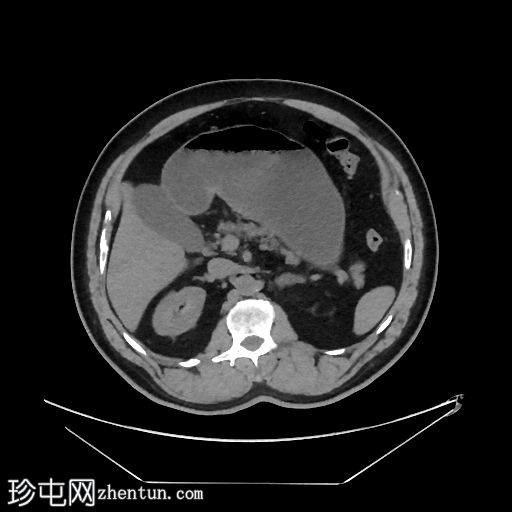

矢状位增强扫描(门静脉期)

胃和十二指肠明显扩张,充满液体,直径约53毫米,可见斑驳状气体样肿块。

十二指肠第四段为移行区,其后为塌陷的空肠和回肠袢。

在CT扫描中,胃石引起的梗阻通常表现为边界清晰的管腔内肿块,在移行点处可见斑驳的气体或“粪便样”外观,并伴有近端肠管和胃扩张,因此CT是最准确的诊断方法。内镜下,植物性胃石通常质地较硬,由压实的食物和植物纤维组成,反映了慢性消化淤积和消化不良。